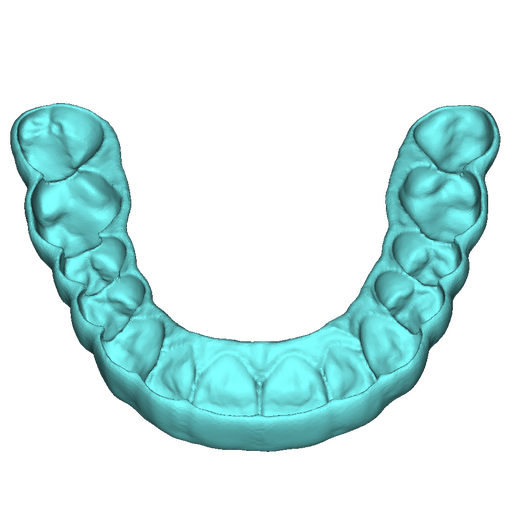

DSD Bite Splint Design

The DSD Bite Splint (night guard) is designed to be worn after a full mouth rehabilitation to protect DSD Natural Restorations and/or DSD Direct composite restorations. The splint design can be used for both milling and printing.

This product is ideal when you need to protect restorations that have already been placed to help avoid possible fractures due to grinding and bruxism.

This is a digital product, delivered in STL format.

An .STL file of the DSD Bite Splint design that can be used for manufacture, either by DSD Lab or your local lab.